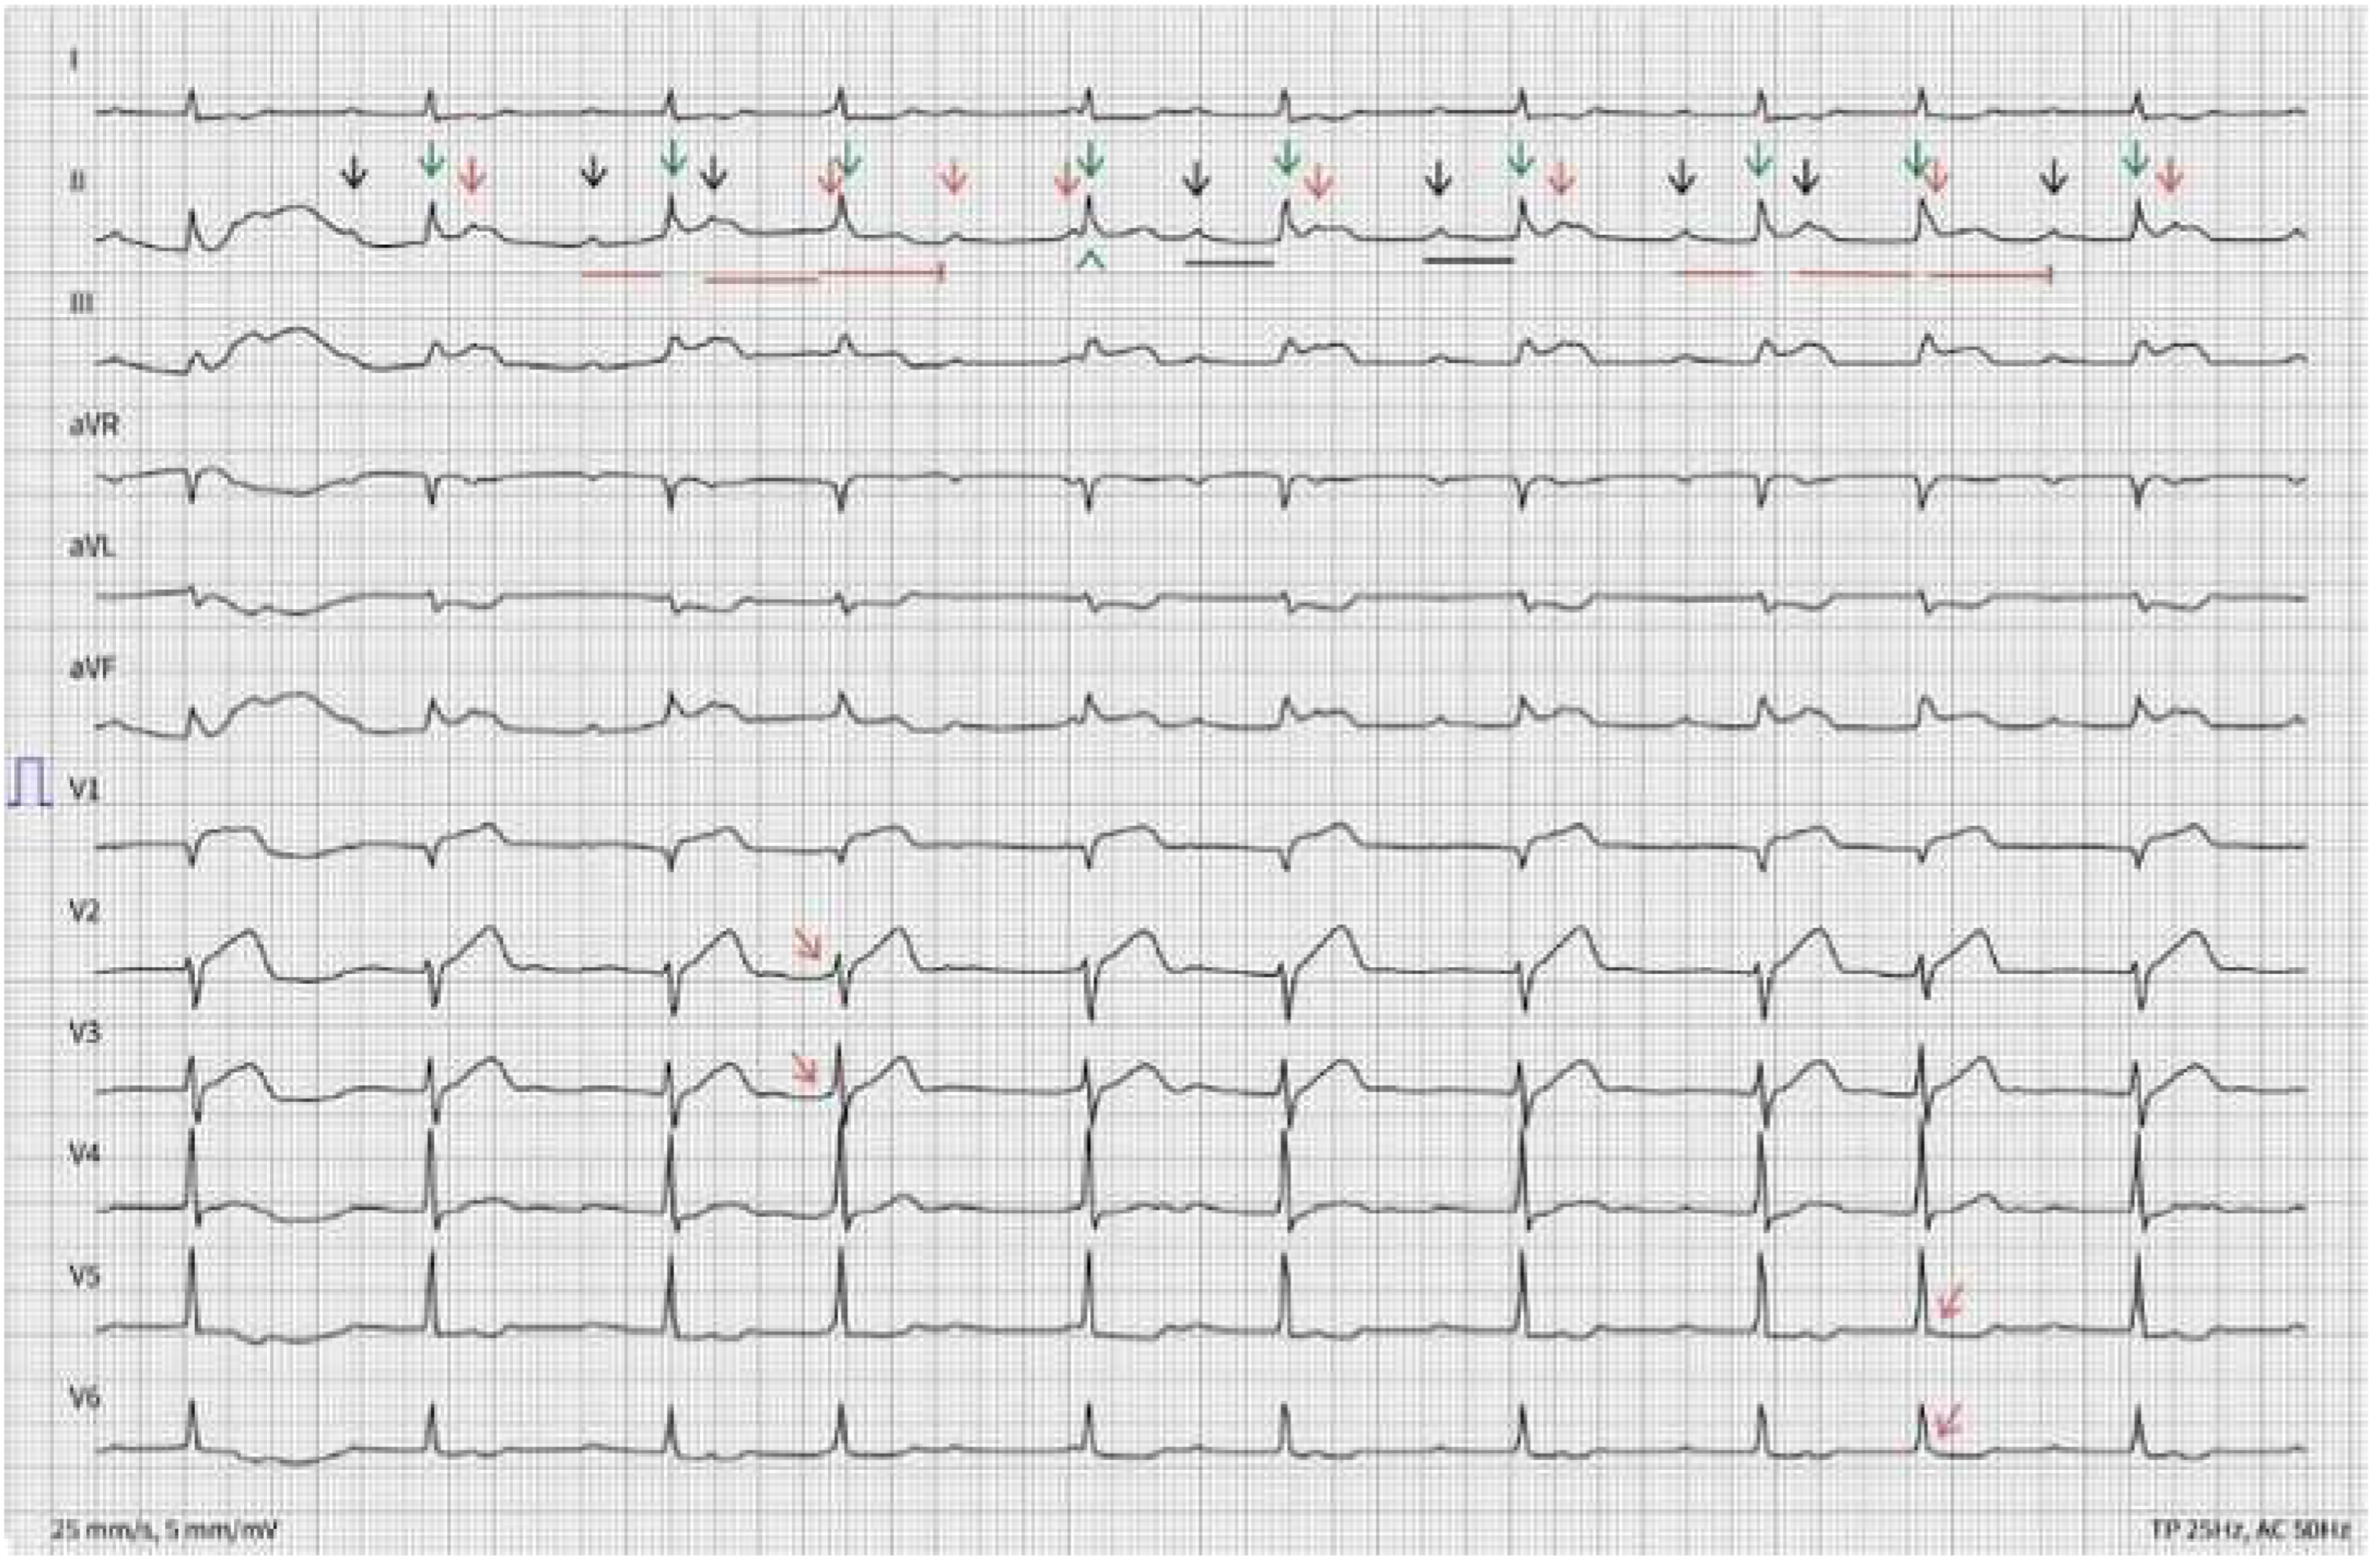

A 56-year-old man with history of hypertension, diabetes mellitus type 2 and chronic kidney disease is evaluated in the emergency department due to nausea, abdominal pain, excessive sudation and lightheadedness for the past 4 h. Physical examination is unremarkable. The following ECGs (ECG A and B) are obtained.

There is an irregular rhythm with a ventricular rate of 61 bpm. QRS complexes are narrow. Big amplitude T-waves are seen in V1 through V3 (circled). There is significant ST segment elevation in leads II-III, aVF and V1 (red arrowheads) with reciprocal ST segment depression in leads aVL, V5 and V6 (black arrowheads). An increased number of P waves (black and red arrows, corresponding respectively to conducted and non-conducted P waves), compared to the number of QRS complexes (green arrows), can be counted. The PP interval is regular. An increasing PR interval (red lines with increasing length) is measured, with a resulting non-conducted P wave (2nd red arrow and terminated red line), compatible with a Wenckebach phenomenon. The non-conducted P wave is merged in the QRS complex and can be better visualized in V2 and V3 (leftward bending red arrows). The following QRS complex (green arrowhead) results from conduction with a very long PR interval or represents a junctional escape beat. The PR interval of the preceding P wave is indeed too short to result in AV conduction. Thereafter, a 2:1 block occurs for 2 cycles (underlined in black), followed by a repeat Wenckebach phenomenon (red lines with increasing length and finally terminated). The blocked P wave is hidden in the QRS complex and can be better spotted in V5 and V6 (rightward bending red arrows).

Based on these ECGs, an inferior ST-segment elevation myocardial infarction (STEMI) with associated atrioventricular (AV) nodal conduction abnormalities is suspected. The ST-segment elevation in lead III > II associated with an ST-segment elevation in V1 suggest an associated right ventricular infarction [1]. Additionally, a 2nd degree Mobitz type I AV block with 2:1 ventricular conduction is present. An intranodal rather than infranodal AV block is suggested, due to the prolonged PR interval and documented Wenckebach phenomenon with 3:2 conduction [2]. A proximal to mid-right coronary artery (RCA) lesion is probable, with resulting ischemia of the right ventricle, as well as the AV nodal artery perfusion area.

ECG A with answer

Cardiovascmed 22 00001 g004